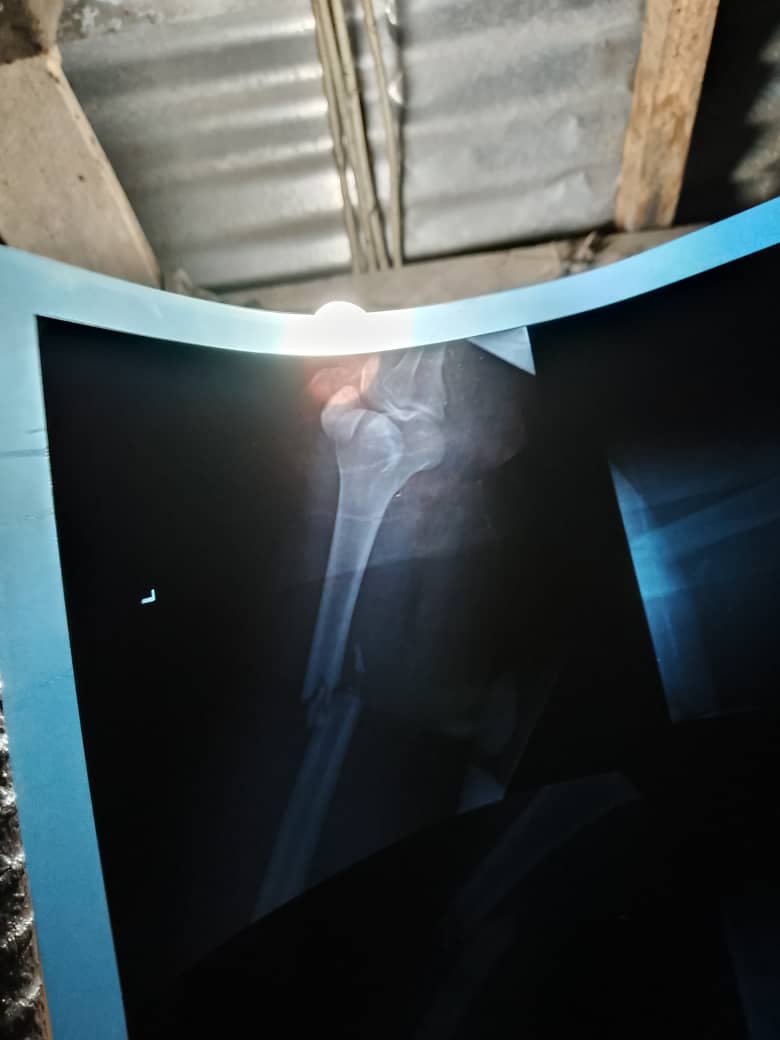

I was booked for surgery but need 1.3M to pay for it @DONJAZZY @asher_kine @romeocza @BETFUSE1 I need your help to walk again

Dear X family I seriously need your help to walk again,I was involved in a ghastly motor accident last year Nov 24th I broke my femur n dislocated my knee I tried the local orthopaedic people but did not get any result I was asked to go for surgery after spending alot at the loca